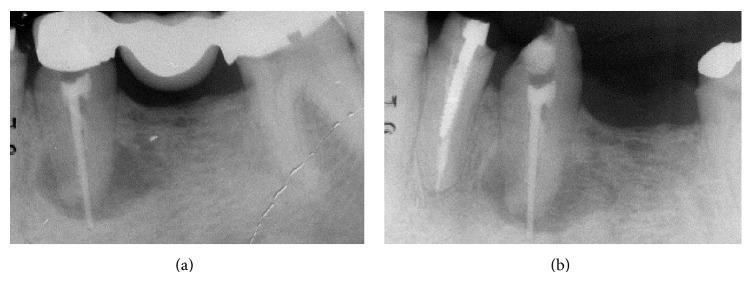

The extraction of teeth results in rapid bone resorption both vertically and horizontally in the first month. The loss of alveolar ridge reduces the chance of implant rehabilitation. Atraumatic extraction, implant placement in extraction socket, and an immediate prosthesis have been proposed as alternative therapies to maintain the volume and contours tissue and reduce time and cost of treatment. The immediate load of implants is a universally practiced procedure; nevertheless a successful procedure requires expertise in both the clinical and the reconstructive stages using a solid implant system. Excellent primary stability and high bone-implant contact are only minimal requirements for any type of implant procedure. In this paper we present a case report using a new type of implants. The new type of implants, due to its sophisticated control system of production, provides to the implantologist a safe and reliable implant, with a macromorphology designed to ensure a close contact with the surrounding bone.